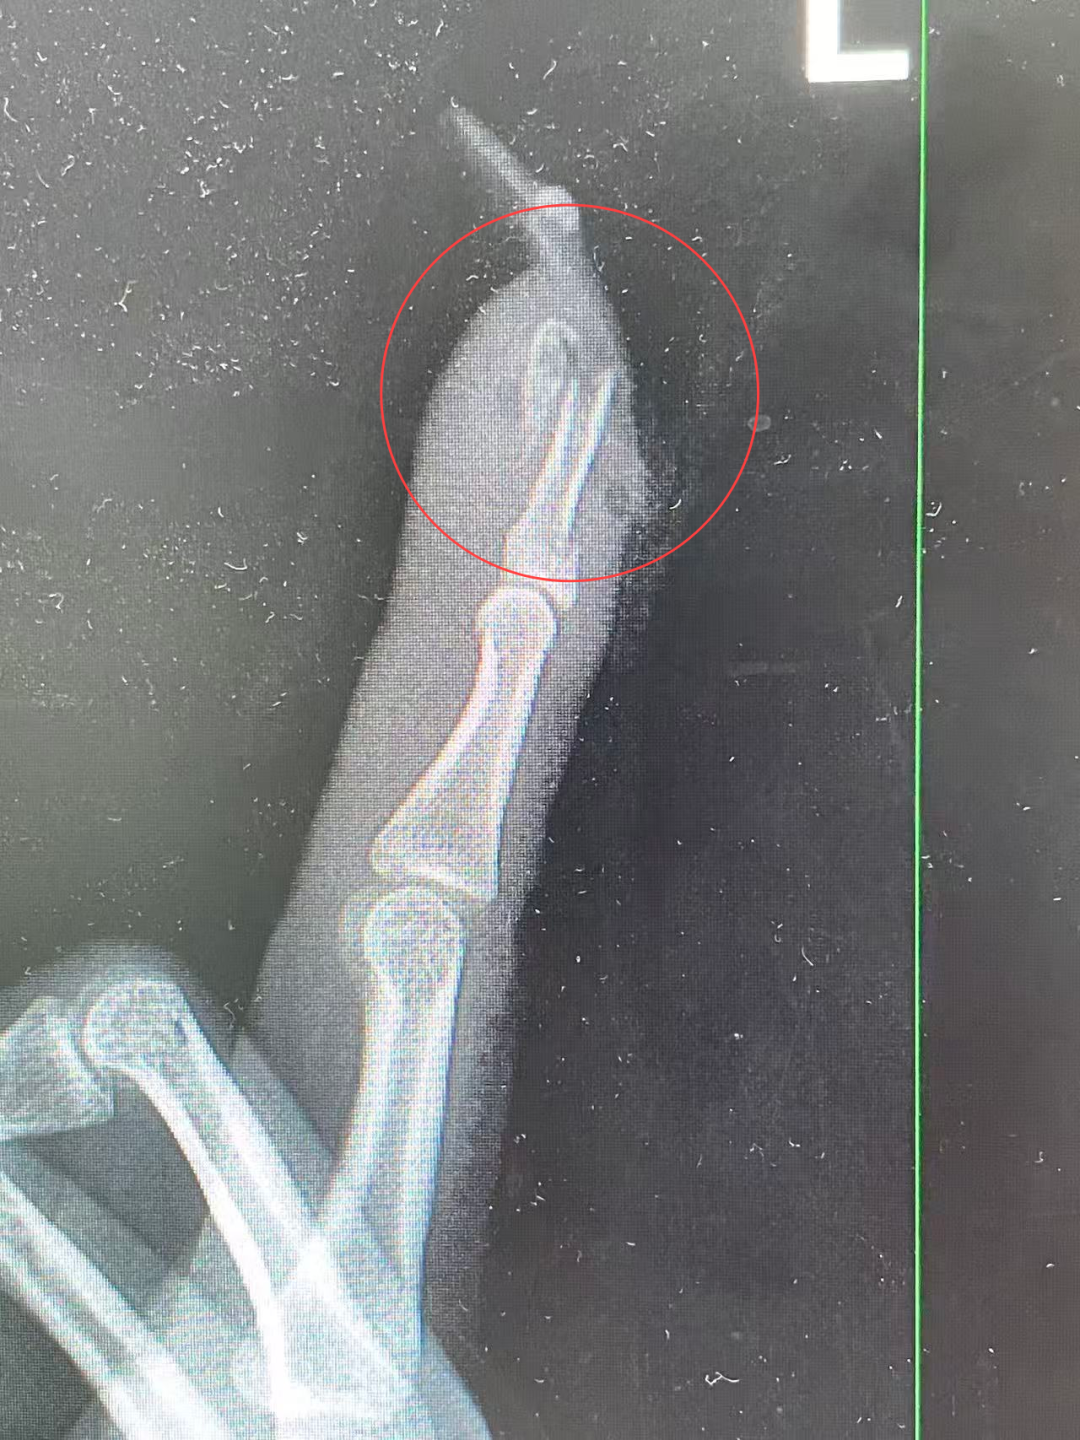

“左手食指指骨骨折,甲床破裂,部分甲床外露,需要手术修复。”接诊医生检查后作出诊断,并当即对其做了指骨骨折闭合复位内固定术。

王小姐术前的X光影像

术后,王小姐情况恢复良好。“如果没有这么细长复杂的美甲,伤害也许不会这么严重。”医生表示,“延长甲片增加了手指的受力面积和杠杆作用,在摔倒时极易形成‘撬动’效应,导致指甲撕脱、甲床损伤,甚至引发骨折。”